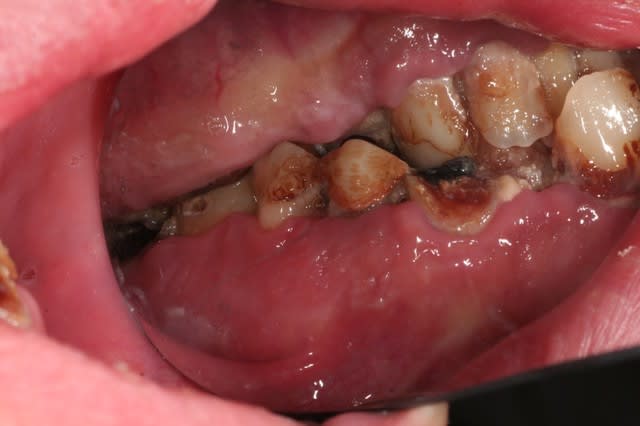

je crois que là, à part dentisterie véto et pédo, tu as tous les thèmes d'eugénol dans une seule bouche.

j'explique le contexte: jeune homme à l'adolescence plutôt difficile, rangé des voitures. s'est mis à son compte.

hyper motivé, à souscrit un crédit pour la totalité des travaux. on démarre dans quinze jours si tout va bien.

va t y sermoner sur l'hbd? grrr... avec delicatesse surement, parceque le jeune homme a visiblement passé beaucoup de temps chez les dentistes, beaucoup de séances, et le resultat...

ensuite comment la mécanique alhounienne va t elle s'epanouir et se révéler? par exemple, mais entre autre, va t y se bagarrer avec cette 34 en reprenant l'endo et en esperant resurrection (c'est jouable), va t y virer et implanter avec le reste (il y a tellement d'os si tentant)? comment l'endo qui est au plus profond de lui va t il se confronter avec l'implanto encore plus enfoui?

Au delà du problème de brossage, le résultat est probablement surtout dû à de l'héroïne en IV, donc si le mec est vraiment guéri (est-ce que c'est seulement possible ?) de son addiction, pourquoi pas ?